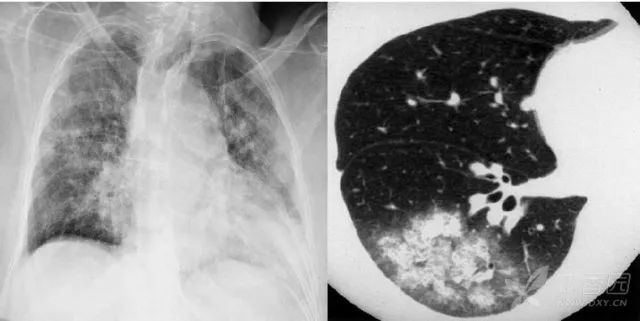

大葉性肺炎胸部影像

簡單來講,肺炎出現(xiàn)較大的病灶,局限在一個肺葉,就叫大葉性肺炎。大葉性肺炎也叫肺泡性肺炎,這是因為大葉性肺炎的炎性滲出主要發(fā)生在肺泡。細菌、病毒、真菌、以及肺炎支原體等非典型病原體都可以引起大葉性肺炎。